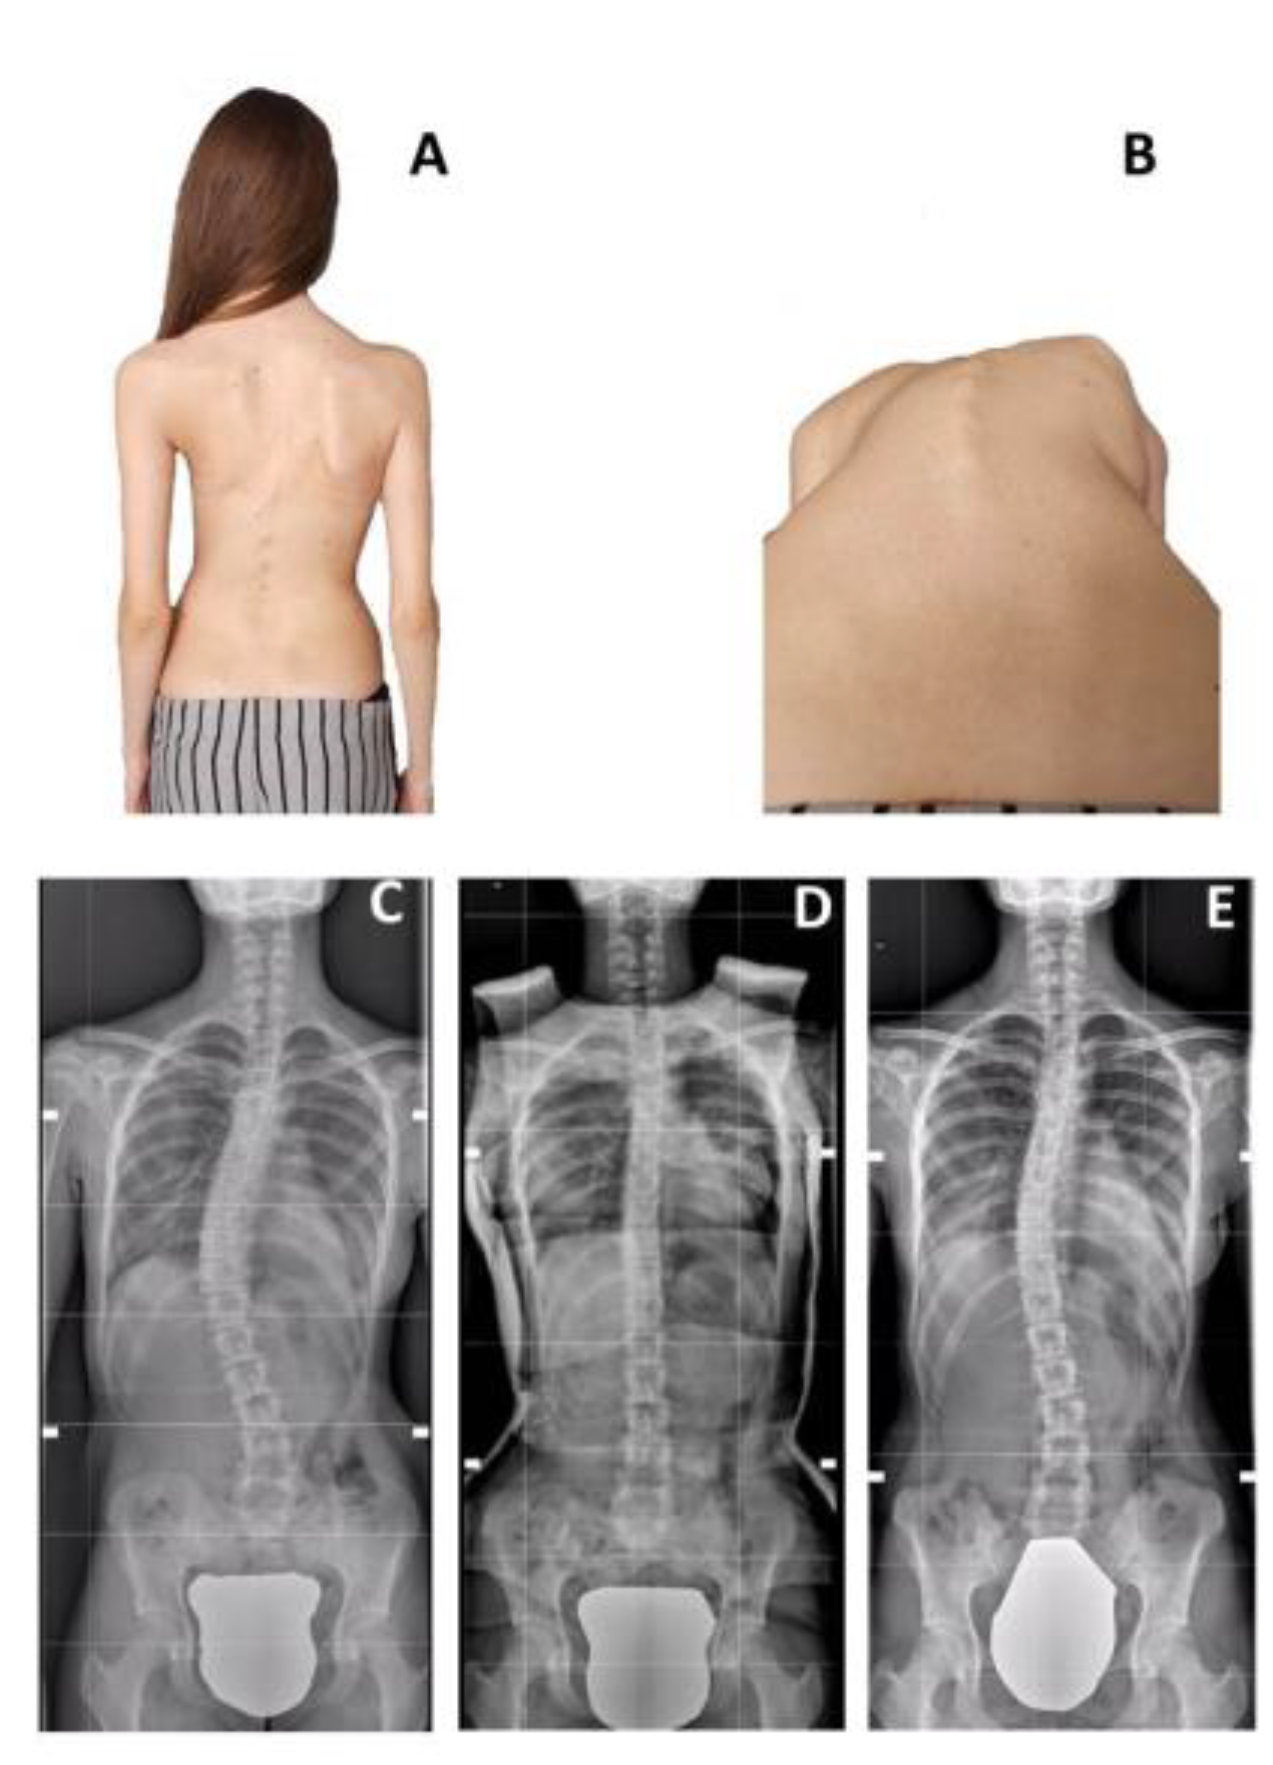

Figure 2.

Case Example for an improved patient in the SG (12 YO Female). Panel (A,B) shows the clinical picture before casting; rib hump is clearly visible; Panel (C) shows the baseline X-ray, with a 41° T Curve, R = 0; Panel (D) shows the in-cast correction; Panel (E) shows the final FU X-ray, with the curve reduced to 26°, R = 5.